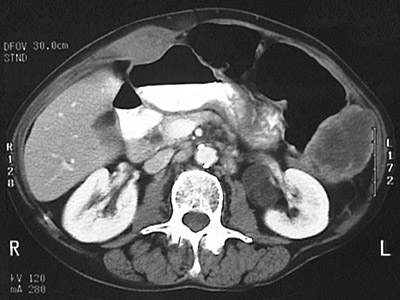

![]() | This abdominal CT scan reveals metastases in the abdominal wall, the left pericolic gutter, the liver hilum adjacent to the gallbladder, and in the retroperitoneum next to the left kidney. The colon is dilated as a consequence of partial obstruction. |